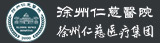

34岁的王云龙是铜山区柳泉镇人,开一家电焊加工店,因为为人诚恳踏实,生意一直不错。1月26日下午4时,他在自家门前用电气焊焊接钢管,操作过程中,钢管突然发生爆炸,王云龙被强烈的震流掀飞出去,靠近钢管的左侧身子遭受重创,左手臂、左腿被炸得血肉模糊,骨头外露,呼啸的120急救车1个半小时后将他送到徐州仁慈医院抢救。

重伤的王云龙送达医院时已经呈失血性休克状态,接诊的手外三病区李刚医生迅速给他展开检查,患者左小腿离断损毁,左大腿粉碎性骨折,骨盆骨折,左前臂不完全离断,左手掌被炸开一个8厘米长的伤口,无名指、小指末节被炸飞,所有手指无血运,伤情危急,需要立即进行急救手术。

术中,李刚手术团队争分夺秒,对患者的左上肢、左下肢展开清创、再植和修复。对左前臂及左手清创、再植,实施左小腿开放性截肢,左大腿清创、肌肉撕脱皮肤修复+骨牵引术。复杂的手术在冷静的手术刀下一步步完成,王云龙被从死亡线上拉了回来。